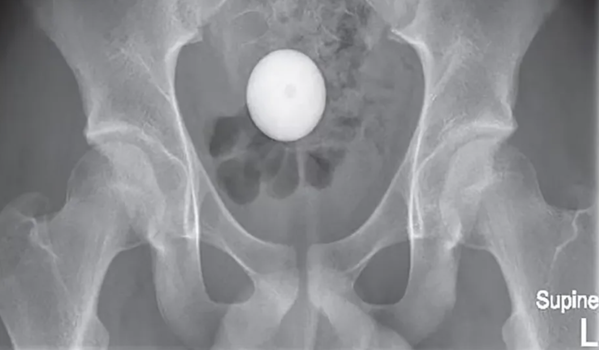

While X-rays seemed to suggest the 14-year-old in Australia had experimented with a white egg, it was, in fact a golf ball. And it was making its way to his sigmoid colon, the last section of the large intestine that connects to the rectum.

It was hoped the ball would “spontaneously enter the rectum”, but an X-ray showed it was still there even 24 hours later.